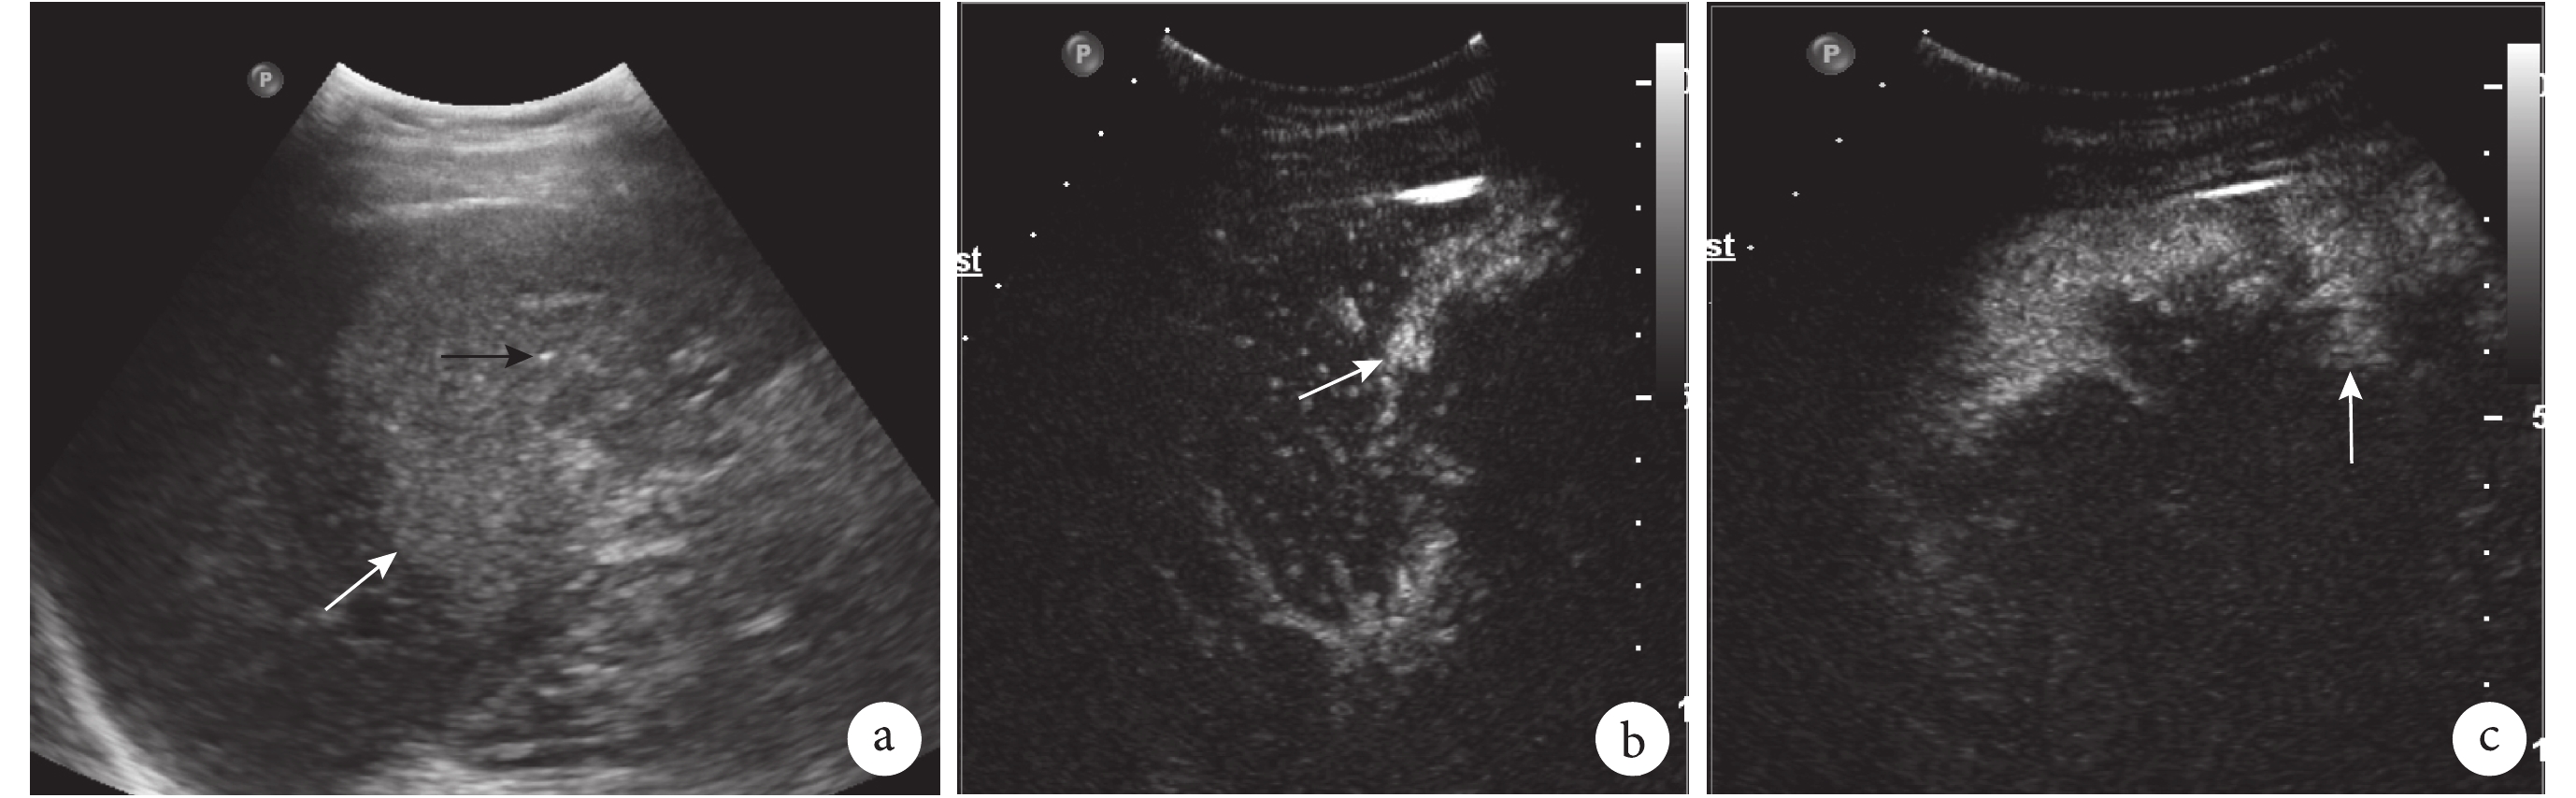

PLC 與 HAE 病灶周邊及內部在不同造影時相的超聲造影表現見表 1。圖 1 及圖 2 分別展示了 PLC 與 HAE 的超聲造影表現。兩組患者在動脈期周邊增強及病灶內部增強間的差異均有統計學意義(P<0.001)。